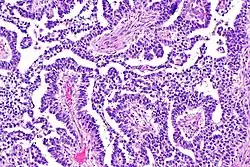

A micrograph view of dysgerminoma, showing actively dividing lobulated nuclei.

Dysgerminomas are comparable to testicular seminomas and account for approximately 32- 37% of all OGCTs.[1] They are particularly prominent in individuals with dysgenic gonads of 46, XY pure gonadal dysgenesis patients.[1] Based on gross examinations, dysgerminomas are characterized by having a ‘solid, lobulated, tan, flesh-like gross appearance with a smooth surface'.[1] Microscopically, the cellular structure is distinguished by a round-ovoid shape containing ample eosinophilic cytoplasm and an irregularly shaped nuclei.[1] The uniformly positioned cells are separated through the fibrous strands and lymphocytic infiltration is commonly observed.[4]